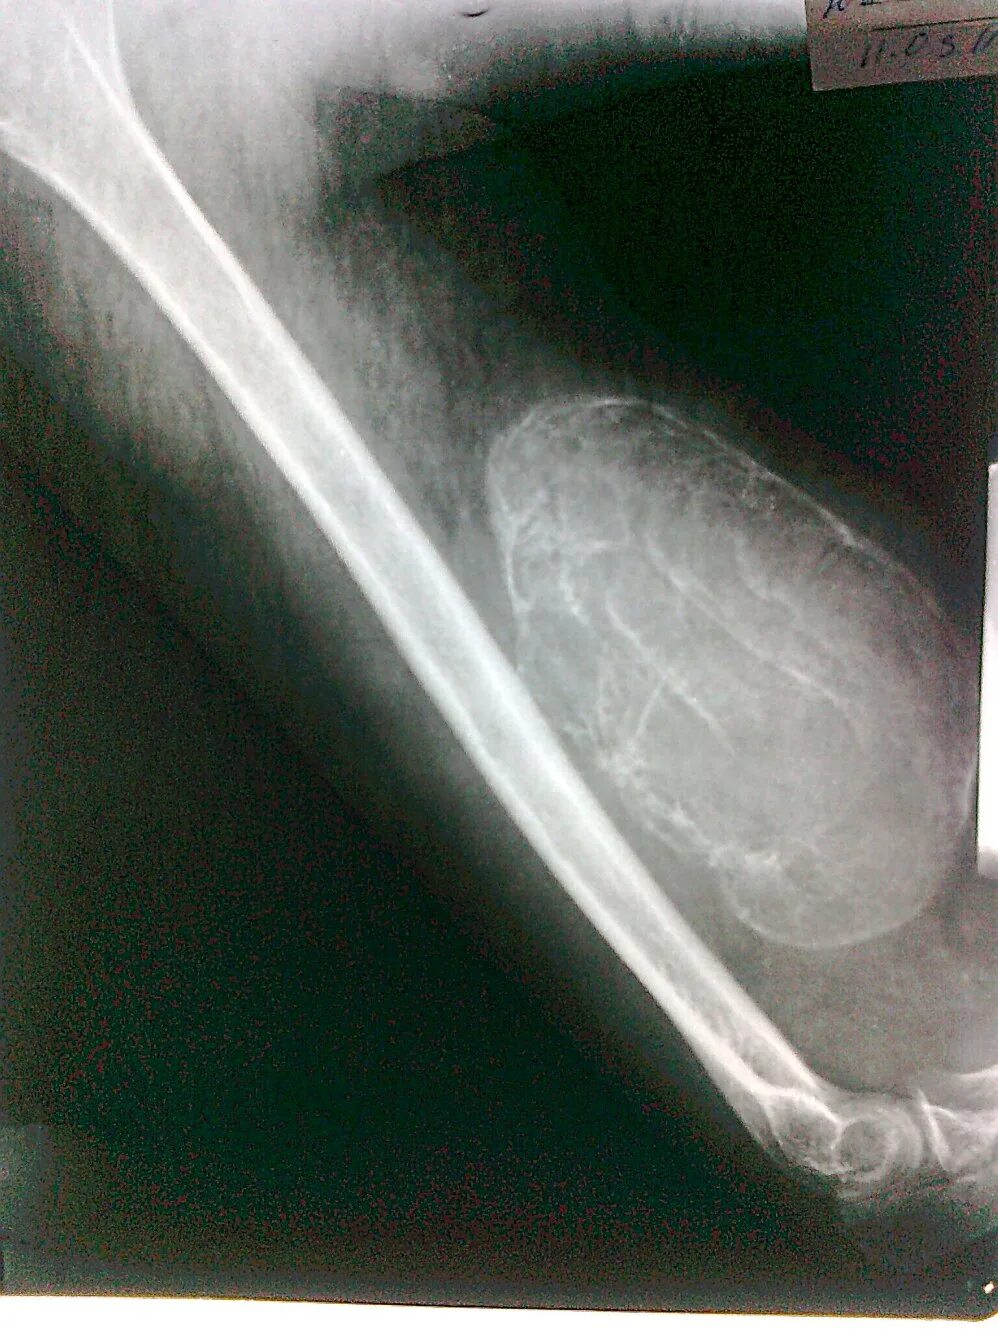

Синовиомы